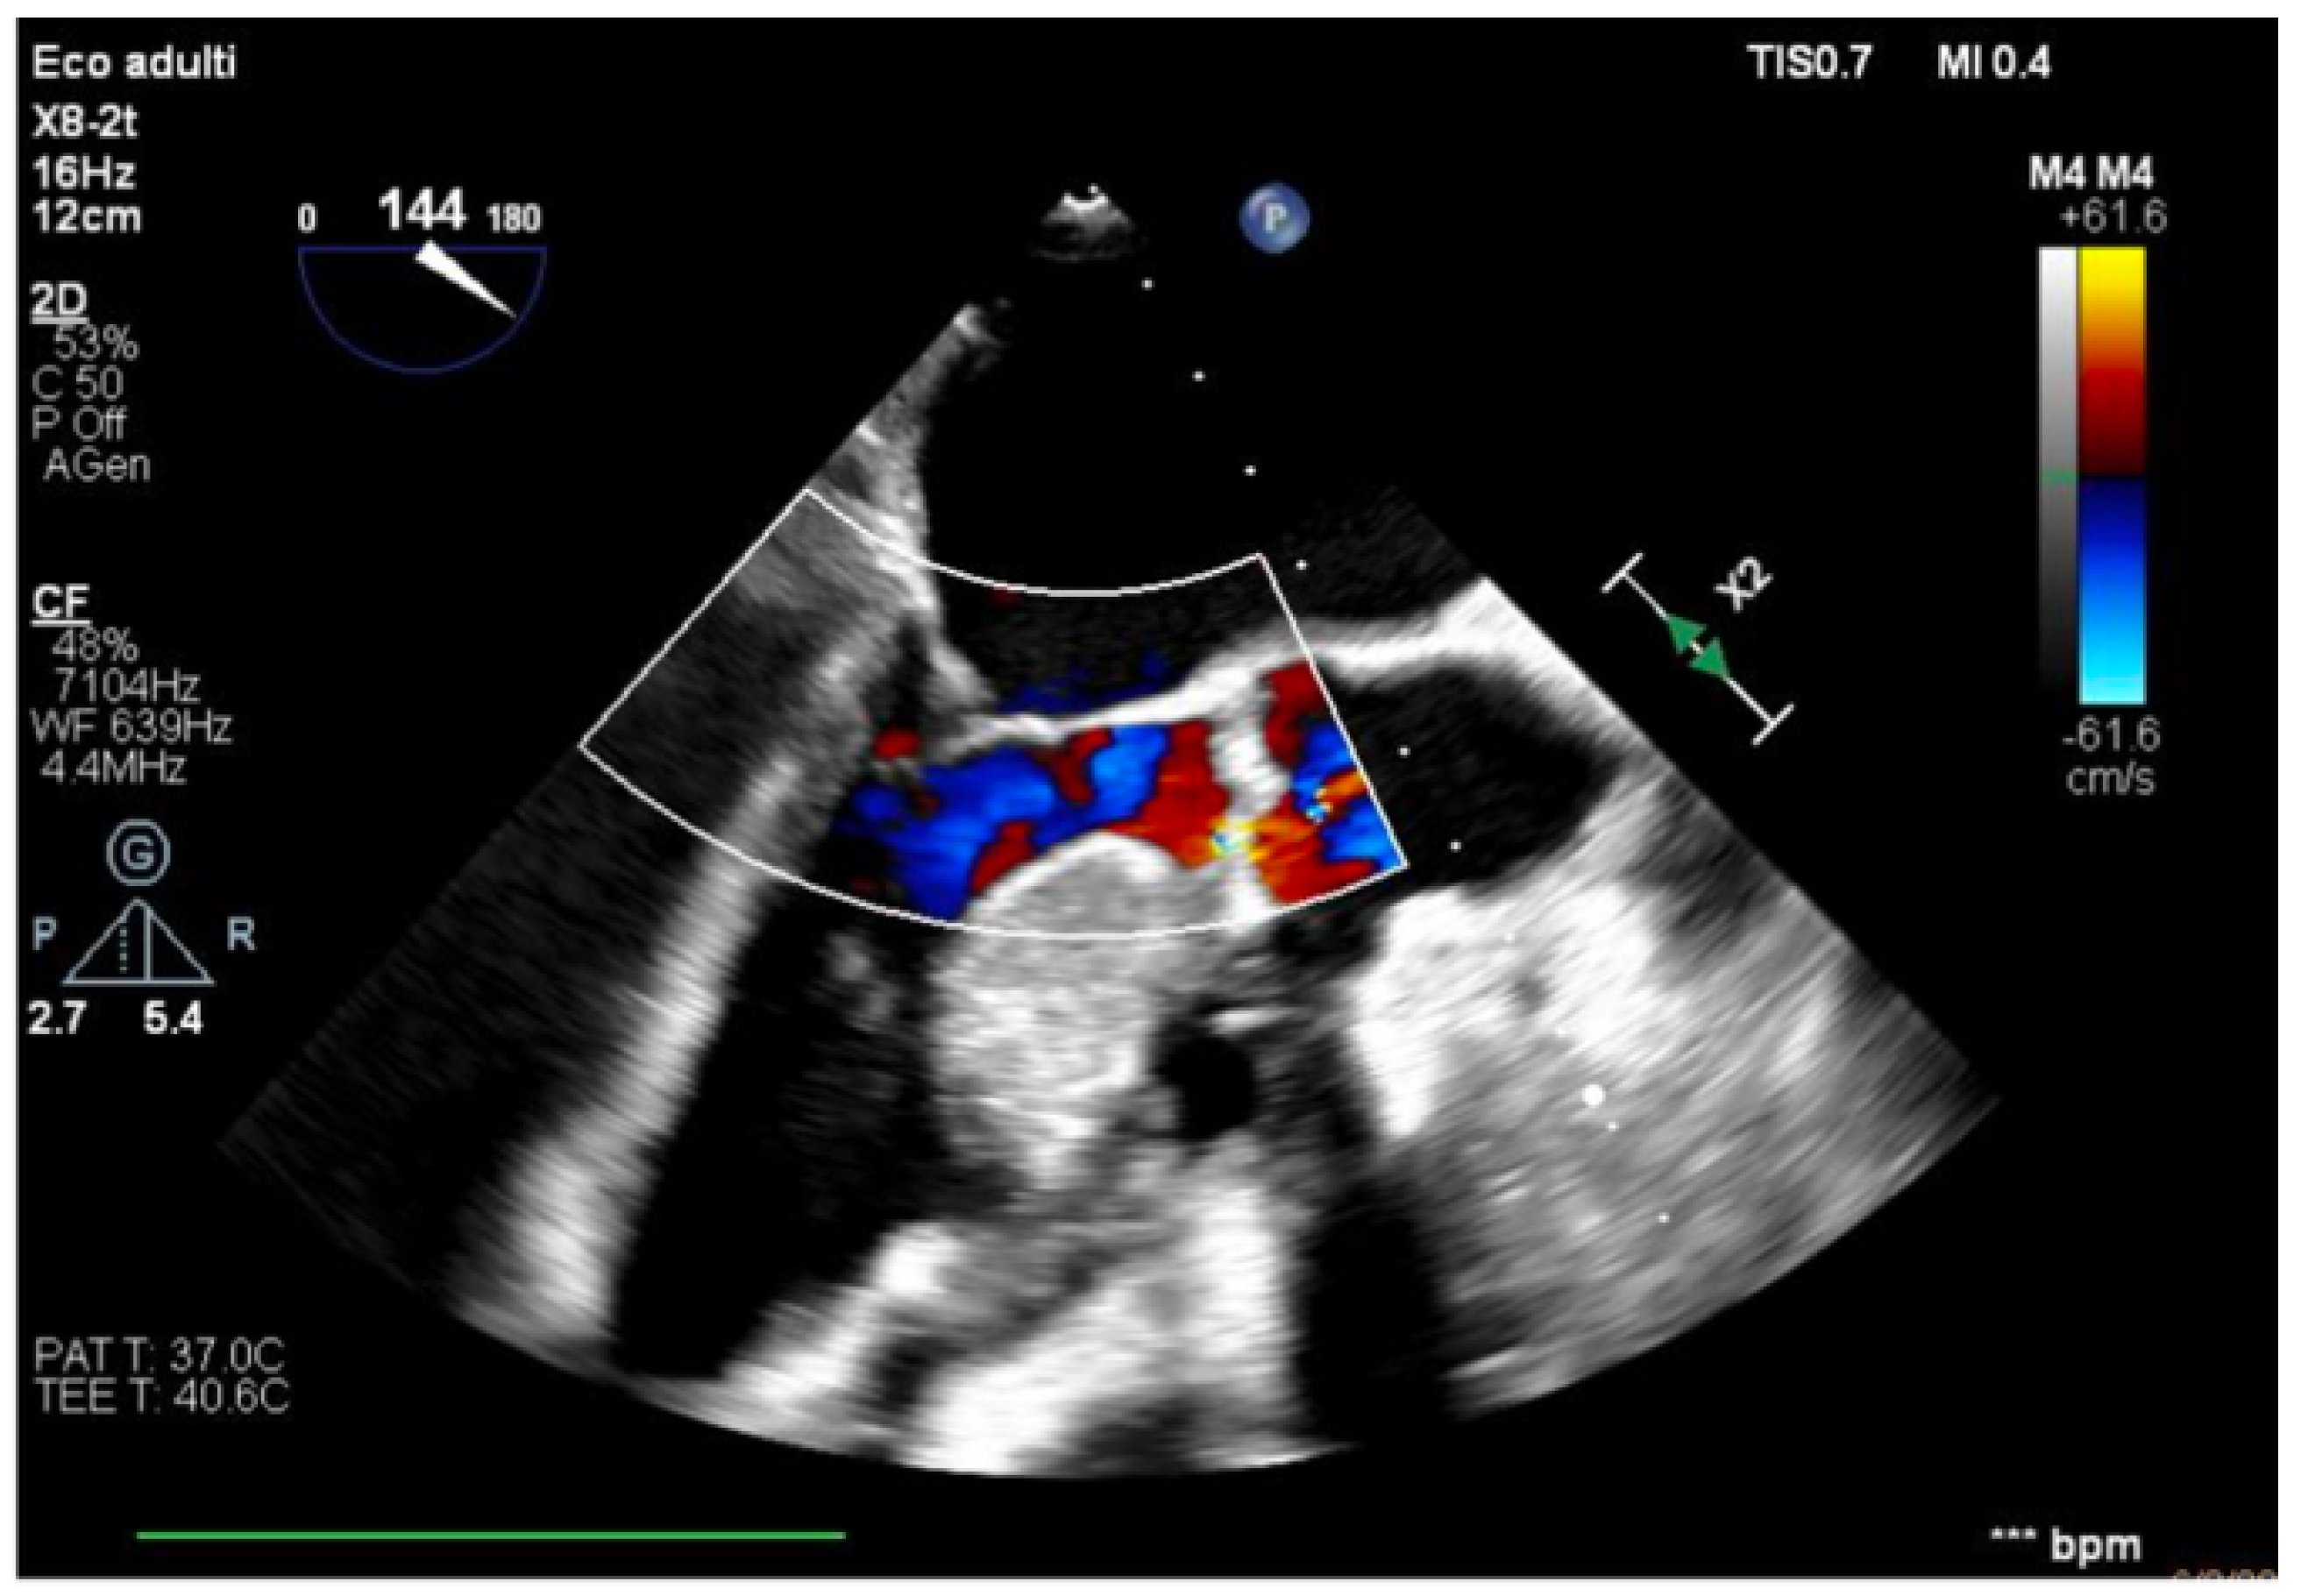

• LV: Improved function of the inferior the lateral walls (LVOT-VTI 15 cm, MAPSE 0.8 mm, e’ lateral 6 cm/s).

Figure 4. Long-axis view, improved function of the inferior–lateral wall.